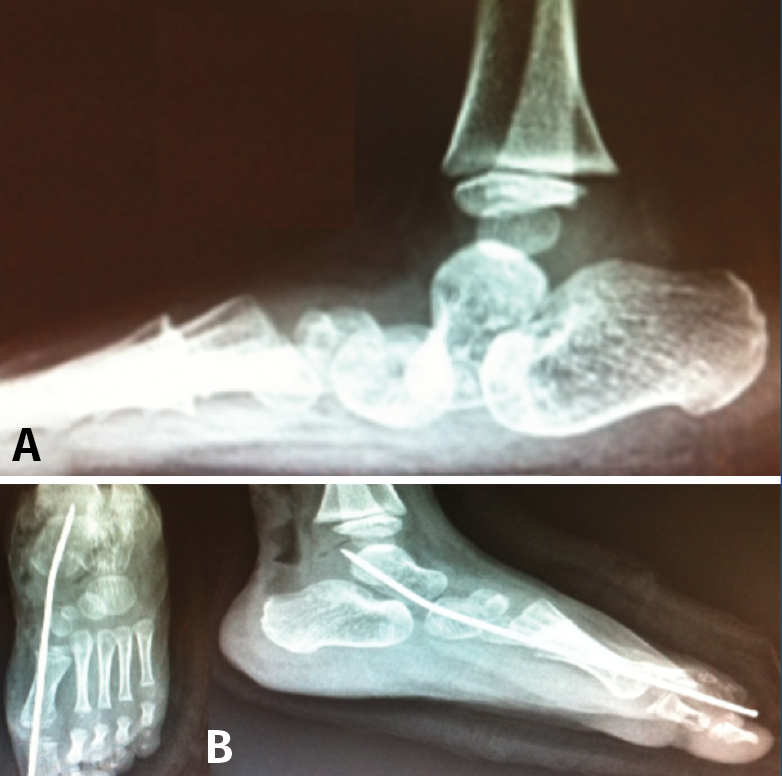

Técnica quirúrgica (Figura 13)

La osteotomía es perpendicular a la cara lateral del calcáneo y oblicua hacia anterior desde el borde dorsal de la tuberosidad mayor hasta su borde plantar. Aunque clásicamente se realiza esta osteotomía de forma abierta, actualmente se puede realizar de forma percutánea. Mediante maniobra externa realizamos una medialización de al menos 1 cm, más osteosíntesis con AK o tornillos canulados de esponjosa(11).

Figura 13. Osteotomía de deslizamiento medial del calcáneo. Escopia intraoperatoria lateral y axial de retropié donde se visualiza la osteotomía de deslizamiento medial del calcáneo.